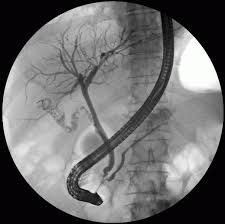

ERCP (Endoskopik Retrograt Kolanjio Pankreatigografi); Özel ışıklı bir aletle oniki parmak barsağında bulunan safra kanal ağzına kadar gelip, bu alet içinden geçirilen özel kanuller, kataterler aracılığı ile safra kanalları, safra kesesi, pankreas kanallarını görüntülemek ve gerektiğinde tedavi edici uygulamaların yapıldığı işlemdir.

- Tanısal amaçlı ERCP'de safra yolları ve pankreas yollarının görüntülenmesini sağlayacak ilaç verilir

- Labaratuvar ve görüntüleme teknikleri ile nedeni tam ortaya konulamayan bazı sarılıkların ayırıcı tanısında

- Safra akımının engellendiğinin saptandığı ancak labaratuvar ve görüntüleme teknikleri ile nedenin tam ortaya konulamadığı durumlarda